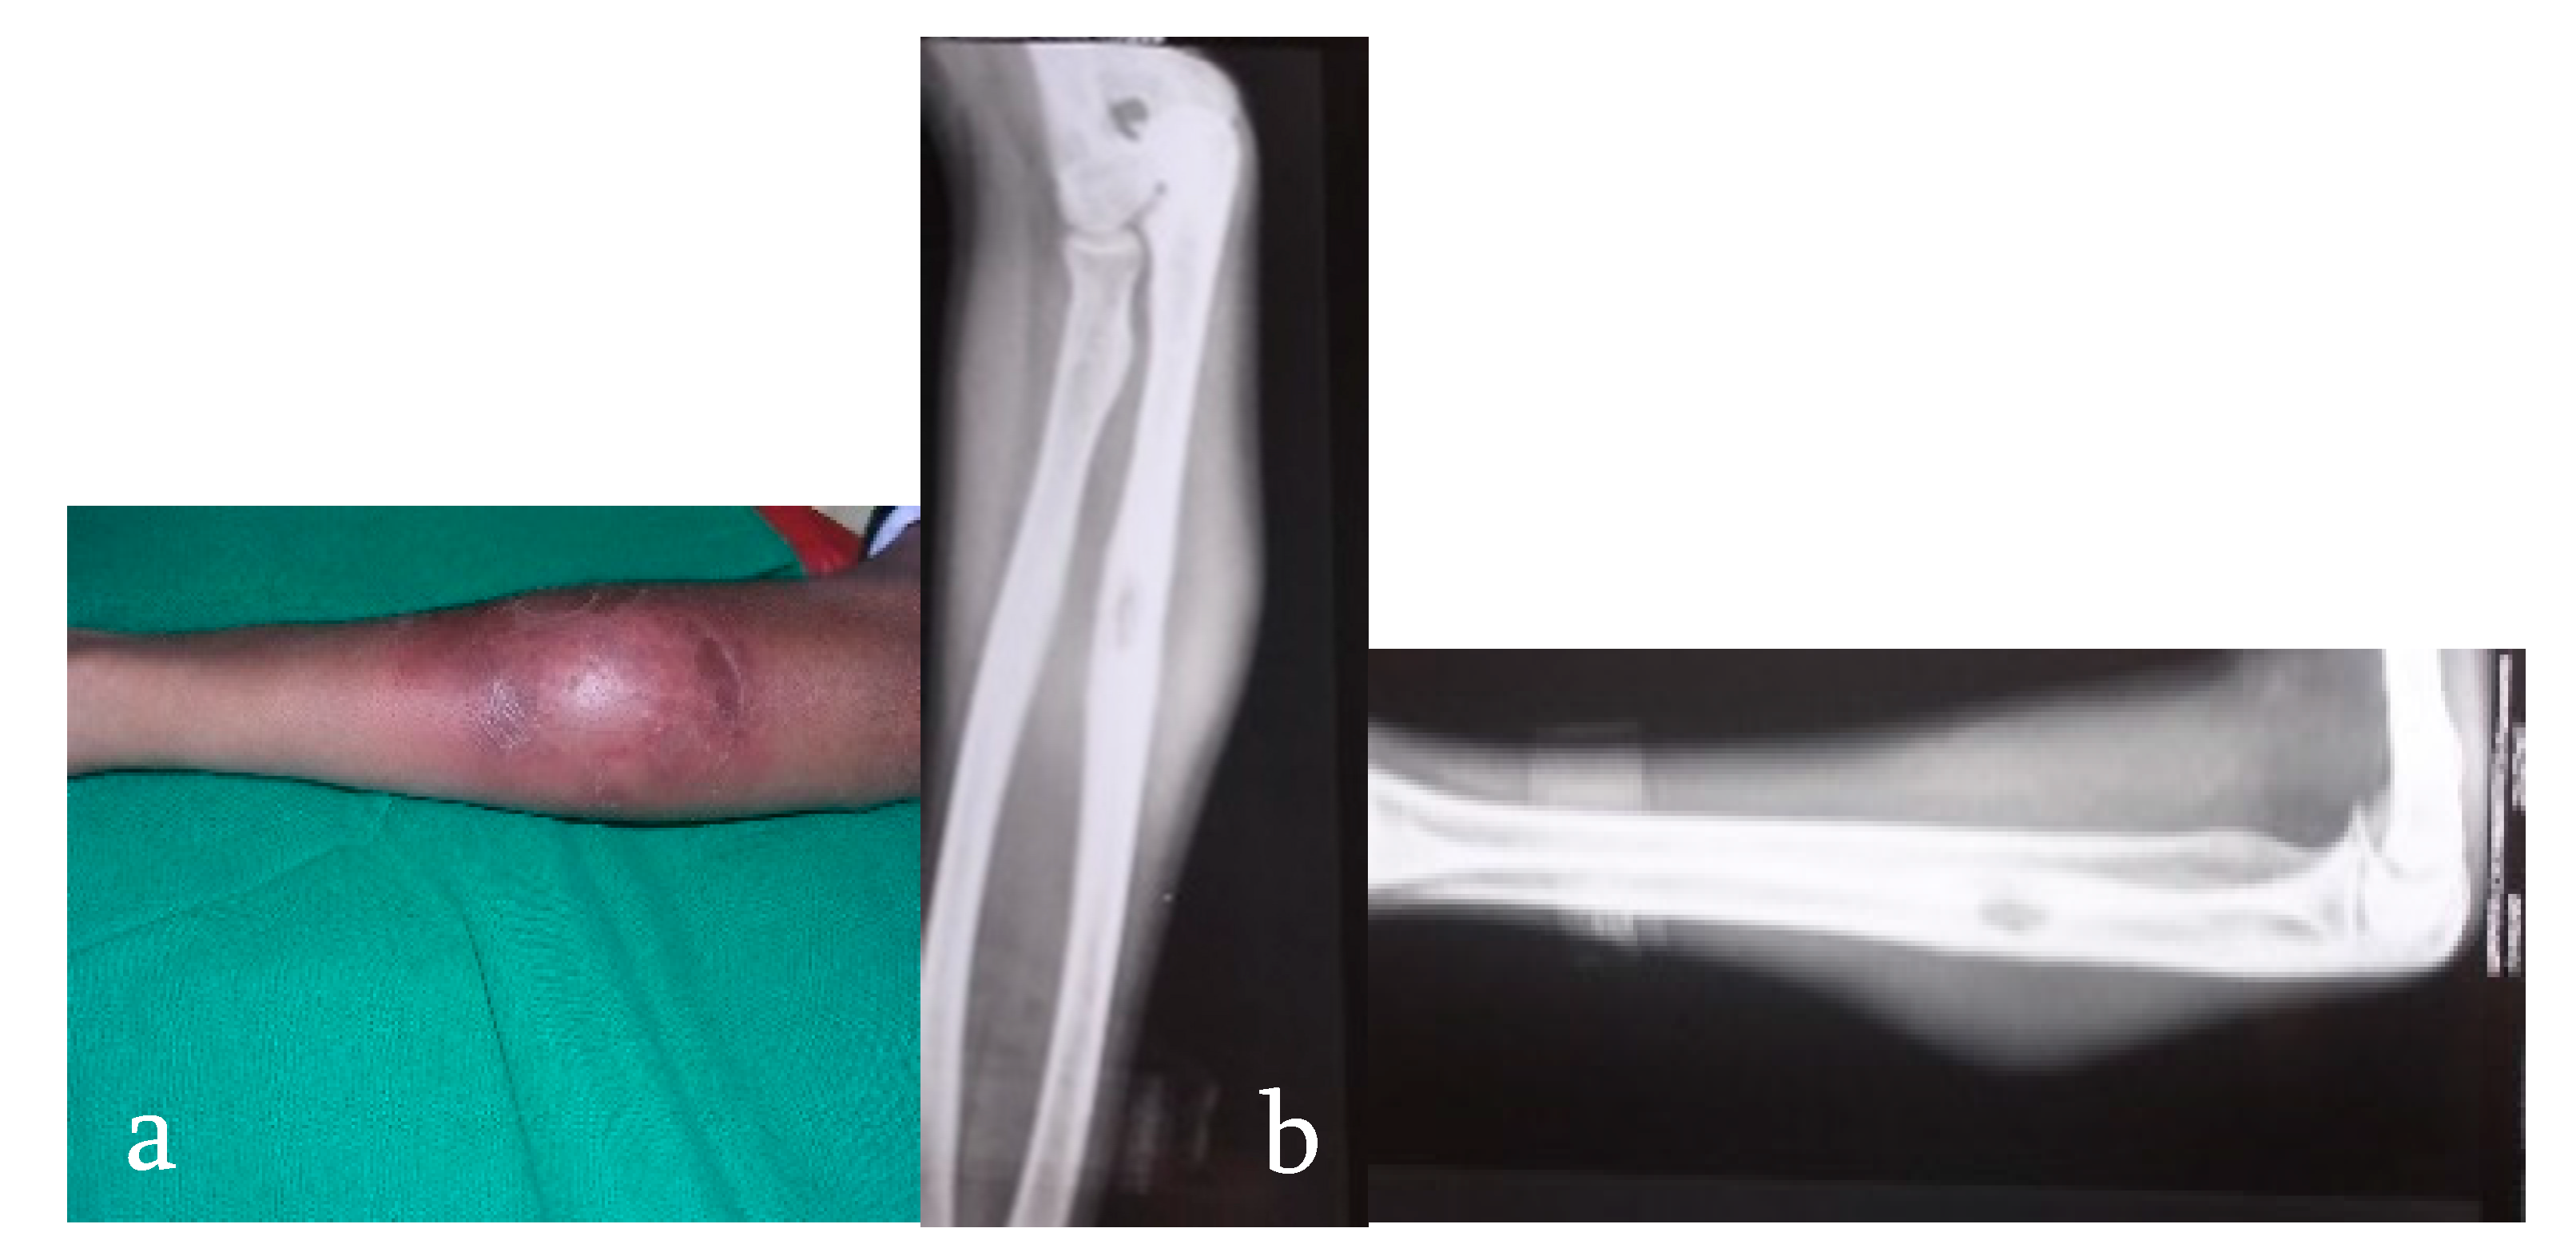

- Stage of synovitis. Patient presents with night pain and spasm of the affected group of muscles. Affected joint has >75% of the joint movement preserved. X-ray shows rarefaction and haziness of the articular regions. This stage has excellent prognosis.

- Stage of early arthritis. Patient presents with joint pain, spasm of the surrounding muscle, and difficulty in doing some activities of daily living. Affected joint has 50–75% of the joint movement preserved. X-ray shows classical Phemister’s triad of juxta-articular osteopenia, mild joint space reduction, and peripheral osseous erosions. This stage has good prognosis with mild stiffness.

- Stage of late arthritis. Patient presents with joint pain, spasm, and difficulty in activities of daily living. Affected joint has >75% loss of range of movement of the joint. X-ray shows marked joint space reduction and joint destruction. This stage has fair prognosis with severe loss of motion.

- Stage of advanced arthritis with subluxation and dislocation. Patient presents with deformity of the involved joint. Affected joint has gross restriction of all movements. X-ray shows pathological dislocation with wandering acetabulum in the hip. This stage has poor prognosis.

- Terminal or sequelae of arthritis. Fibrous ankylosis of the joint is seen.